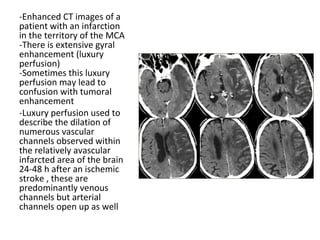

-Enhanced CT images of a

patient with an infarction

in the territory of the MCA

-There is extensive gyral

enhancement (luxury

perfusion)

-Sometimes this luxury

perfusion may lead to

confusion with tumoral

enhancement

-Luxury perfusion used to

describe the dilation of

numerous vascular

channels observed within

the relatively avascular

infarcted area of the brain

24-48 h after an ischemic

stroke , these are

predominantly venous

channels but arterial

channels open up as well

CT+C , infarction in the territory of the MCA , there is extensive gyral

enhancement (luxury perfusion) , sometimes this luxury perfusion

may lead to confusion with tumoral enhancement